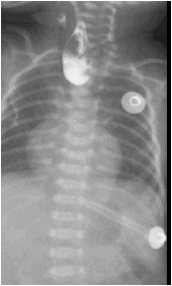

图 2 术后造影提示吻合口漏

2021-08-25 头颅超声:早产儿脑。CR 检查: 胸部 (正位), 腹部 (正位):食道闭锁术后:右侧胸壁皮下少量积气基本吸收;右肺上叶肺不张;新生儿肺炎较前稍吸收;肠管充气明显减少,建议随诊。CR 检查: 胸部 (正位), 腹部 (正位):食道闭锁术后:食道吻合口漏;右侧胸壁皮下少量积气基本吸收;右肺上叶肺不张,较前变化不大;右肺中野内带炎症较前加重。肠管充气少。

给予万古霉素抗感染治疗。9.5 腹部彩超:胃内可见少量内容物,余肠管肠腔萎瘪,走形迂曲;腹腔未见明显肠套叠、肠梗阻及阑尾炎征象。9.13 食管造影:食道闭锁术后改变,吻合口漏。贲门位置抬高,建议随诊肺炎。2021-09-28 造影检查: 食管造影:食道闭锁术后改变,吻合口漏,较前稍好转。贲门位置抬高,建议随诊;肺炎;先天性心脏病。磁共振检查 (1T 以上不含 1T): 颅脑 (磁共振功能成像, 平扫):早产儿脑,左侧侧脑室后角室管膜下局灶性脑损伤,小脑幕缘硬膜下少量出血。